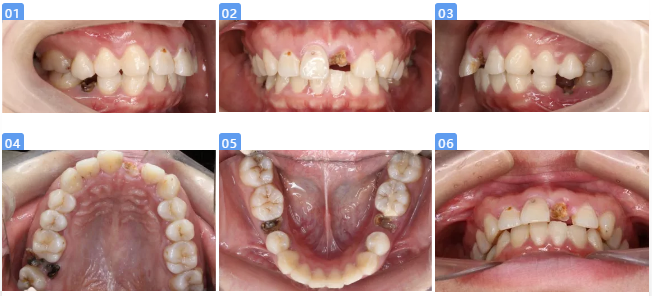

二、临床检查

—前牙残根(问诊由龋坏发展而来,患者喜碳酸饮料,口腔清洁习惯较差)

—全口牙龈红肿,双侧后牙远中关系、前牙深覆合深覆盖

— 口内残根:17、21、35、45

—龋坏:18O、15DO、12B、11MB、22MB、47O

—面部垂直比例三等份;面部左右基本对称

— 上下唇稍凸,頦唇沟浅